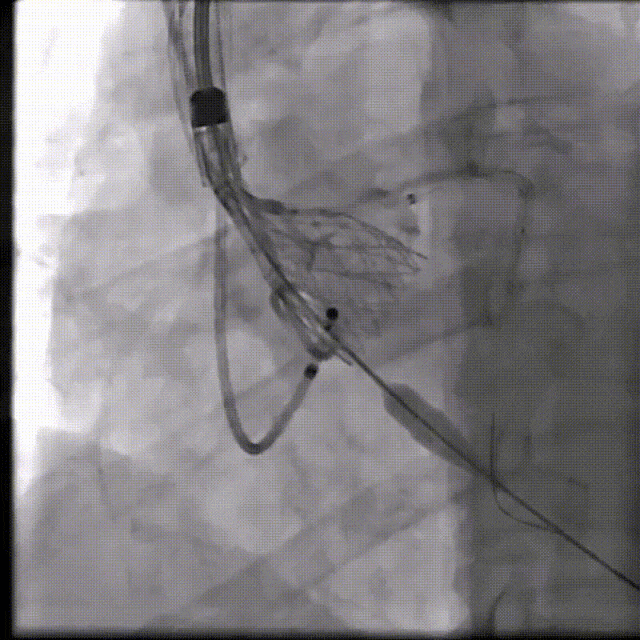

河南省胸科医院心血管内科八病区张由建教授团队在院内超声科、麻醉科、护理科等团队通力协作下,成功完成一例冠脉高风险挑战手术。在团队专业、默契的配合下手术顺利完成,TAVR瓣膜植入良好,患者血流动力学得到明显改善,为患者带来更长久生存期受益和更高生活质量。

(1)Type 0二叶式主动脉瓣,瓣环适中,中度钙化,Type 0二叶瓣受瓣口形态及钙化影响,瓣架呈非理想椭圆形展开,对瓣架支撑力与顺应性提出了更高要求,同时该病例合并升主扩张,对同轴性和释放的稳定性提出了更高的要求。因此优先选择支撑性和顺应性兼具的瓣膜,以及较柔软花冠的瓣膜,降低对升主动脉的损伤,小锥角的设计进一步提升了瓣膜在释放的稳定性

(2)窦部空间较小,左侧瓣叶冗长,且开口位置在短轴平面,左冠冠脉风险较高,优先选择有收腰设计的瓣膜,降低冠脉风险并保留术后足够的VTC

综合病例解剖特点及患者年纪,决定使用第二代可回收的自膨瓣,可回收提高容错空间,为了降低冠脉阻挡风险,决定采用平衡收腰设计的TaurusElite 的瓣膜,先使用大鞘鞘芯进行预扩,然后上20F大鞘。